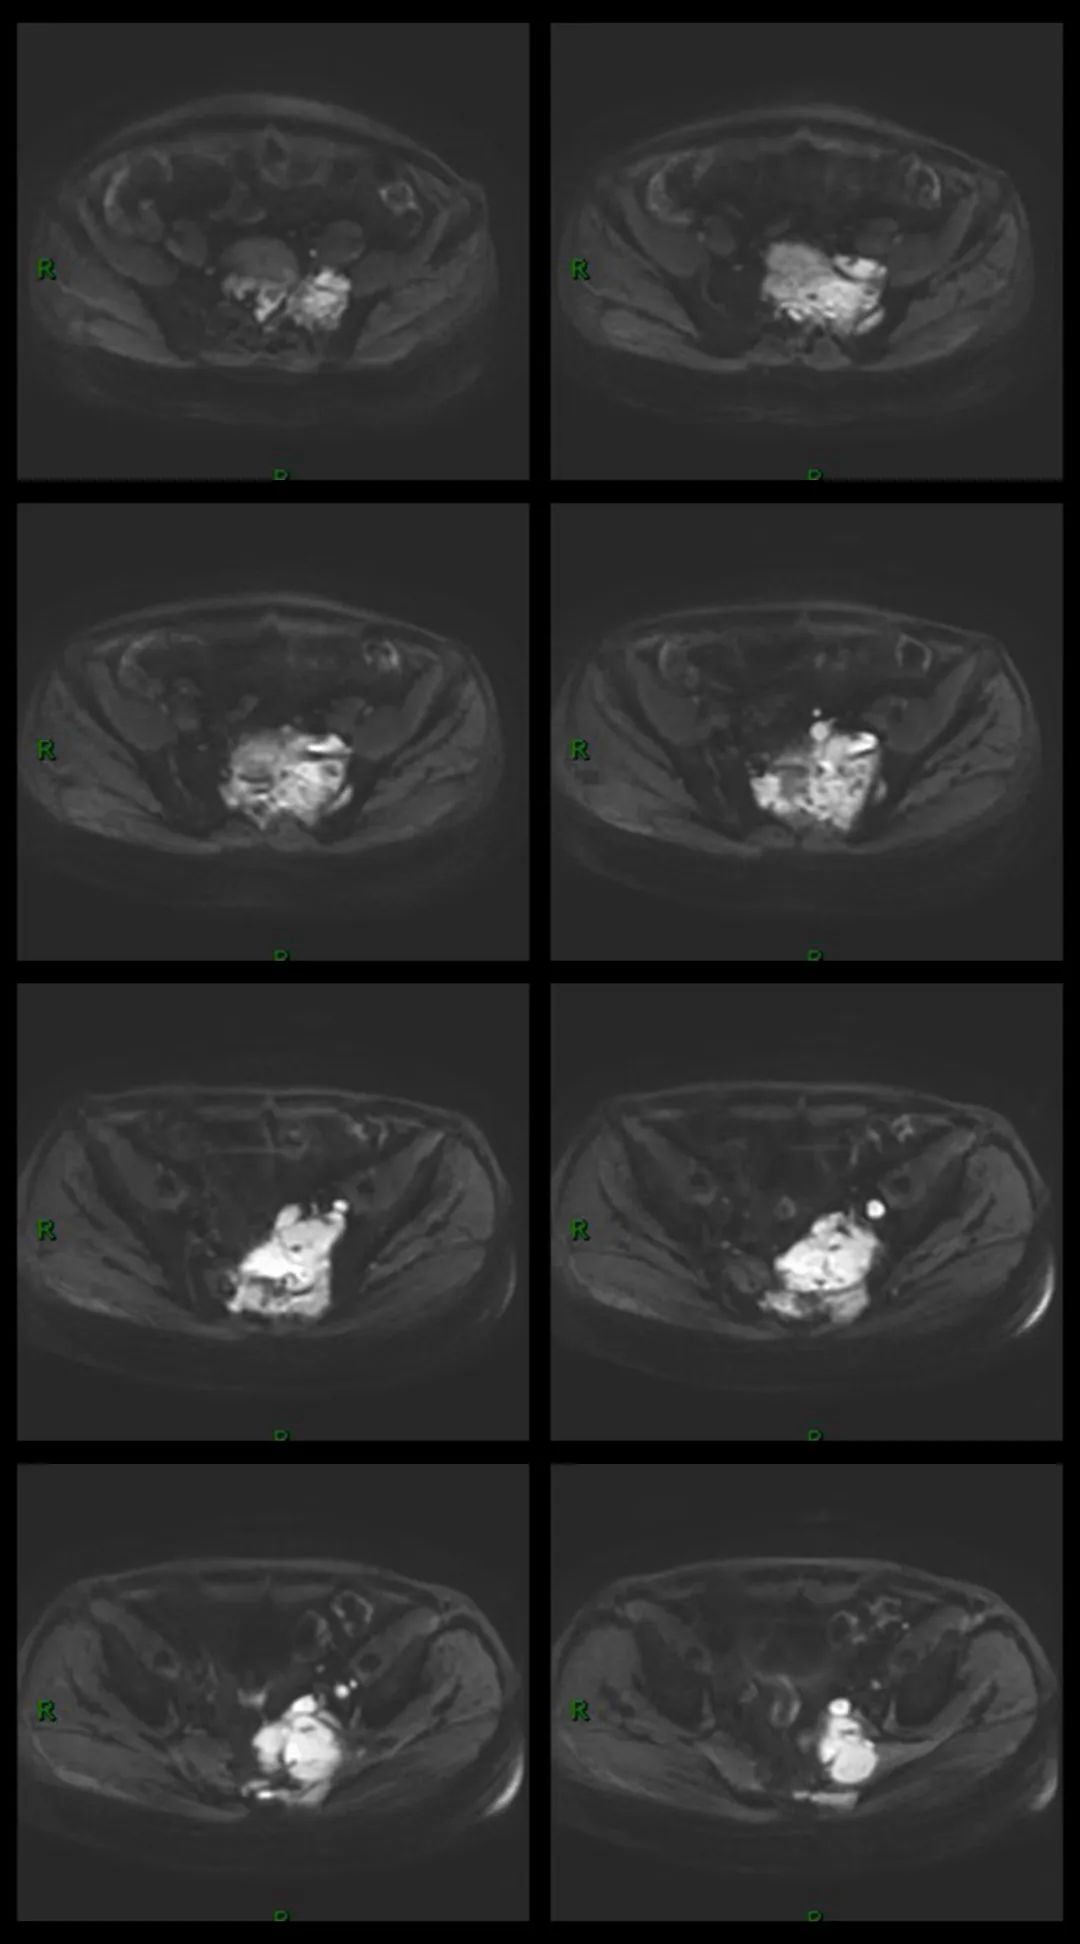

MR 平扫及增强

依据:病灶大,骨质破坏同时突破骨皮质于骨旁形成软组织肿块,骶骨形态存在。病灶骨质破坏相对较轻,而软组织肿块明显。MR 平扫病灶信号均匀,未见明显坏死成分。增强后病灶明显均匀强化。病灶周围可见肿大淋巴结,增强后肿大淋巴结明显均匀强化。

PBL 的 MR 表现:病灶以 T1WI 低或等信号、T2WI 等信号为主,偶呈高信号(细胞排列紧密,水分少),T2WI 压脂呈高信号。淋巴瘤常形成体积较大的软组织肿块,位于椎体者常包绕椎体,并常常累及椎管,因硬膜具有一定阻挡作用,故肿块多位于椎管内硬膜外,可包绕椎管四周生长,形成「袖套」或「肉包骨」样改变。增强肿块一般轻中度均匀强化,坏死囊变少见。